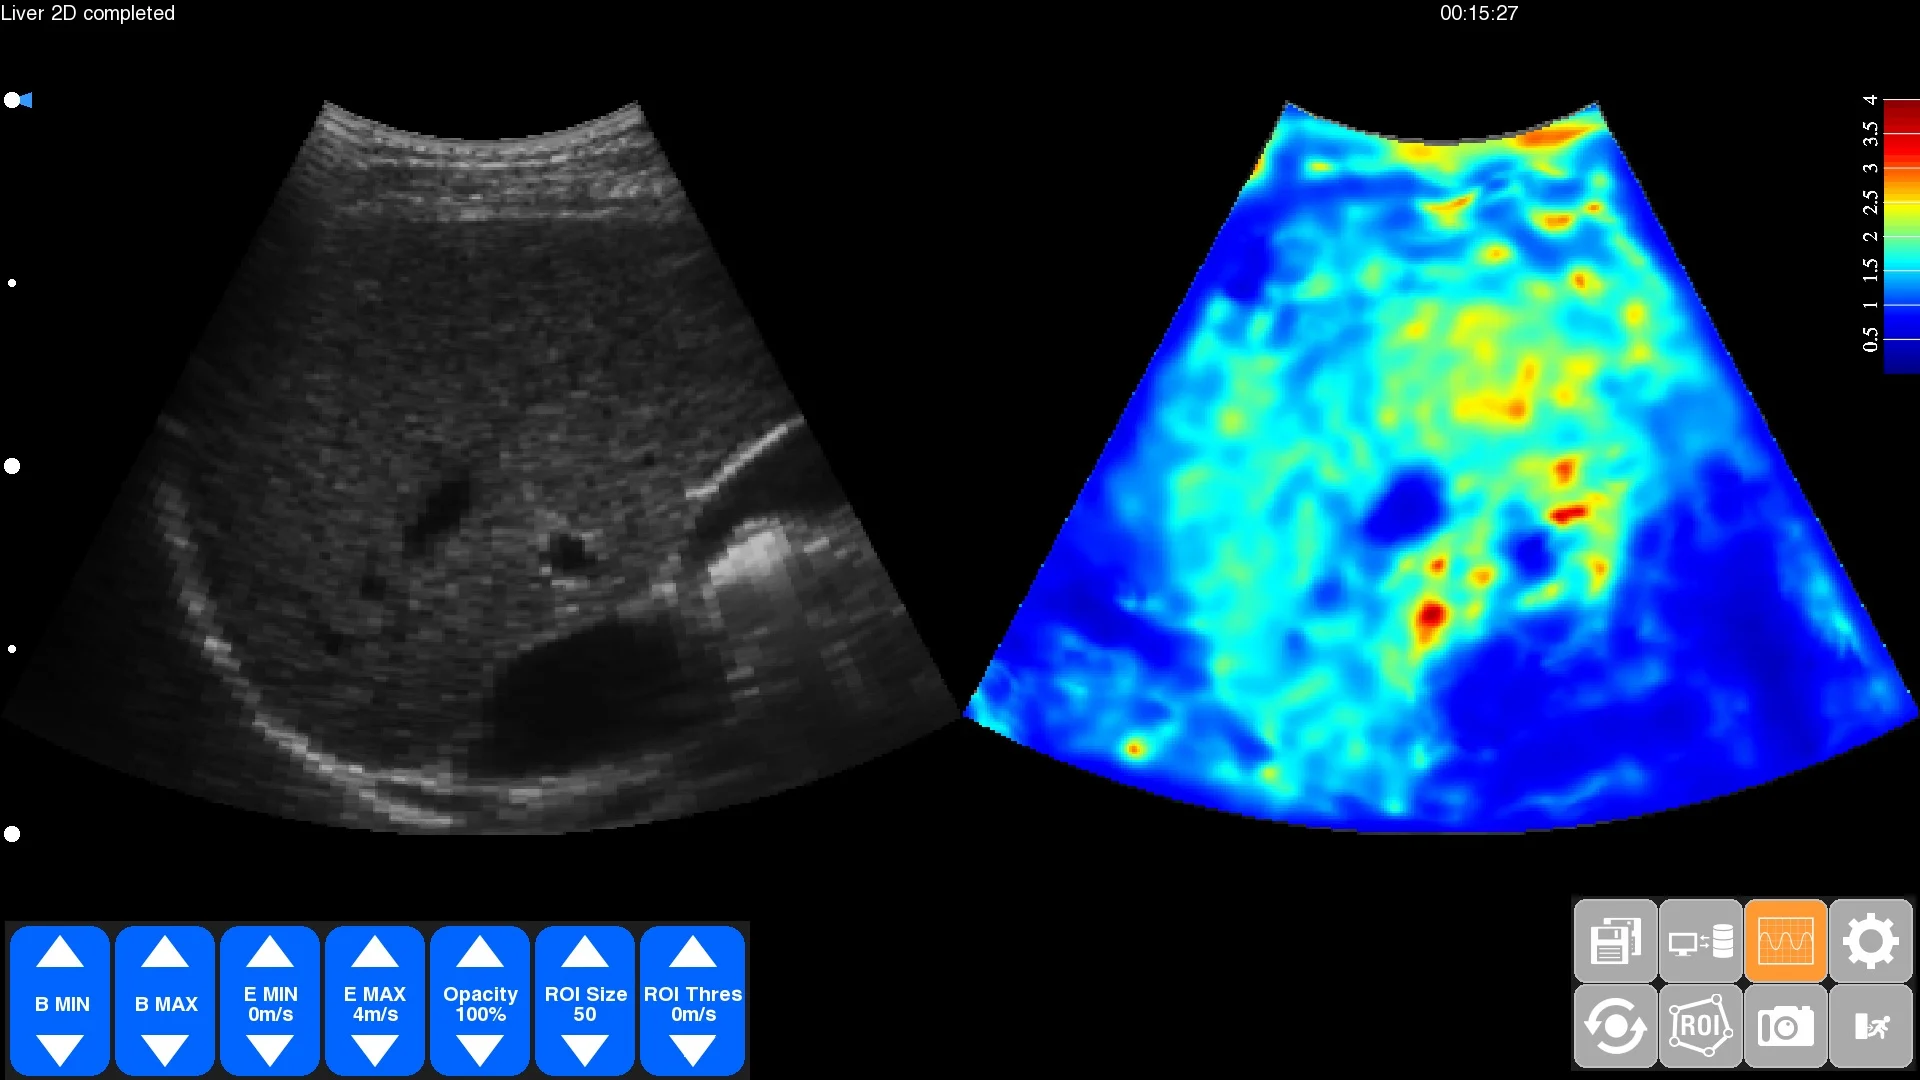

Figure: Side by side display of the ultrasound B mode image with the B mode large elastogram on the THED computer screen. Marked differences of elasticity are shown and are locatable with high precision.

The judgment of spatial relationships is assisted by offering a semi-transparent overlay of the elastogram onto the B mode image. Using side-by-side display with the B-mode image simplifies 2D guidance and increases safety.